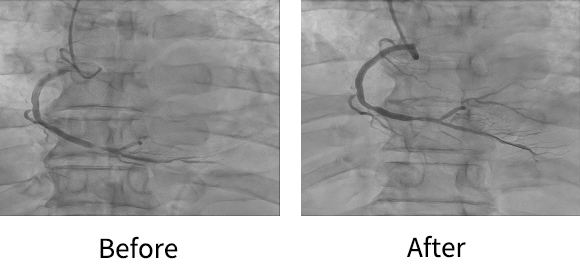

관상동맥 중재술 |